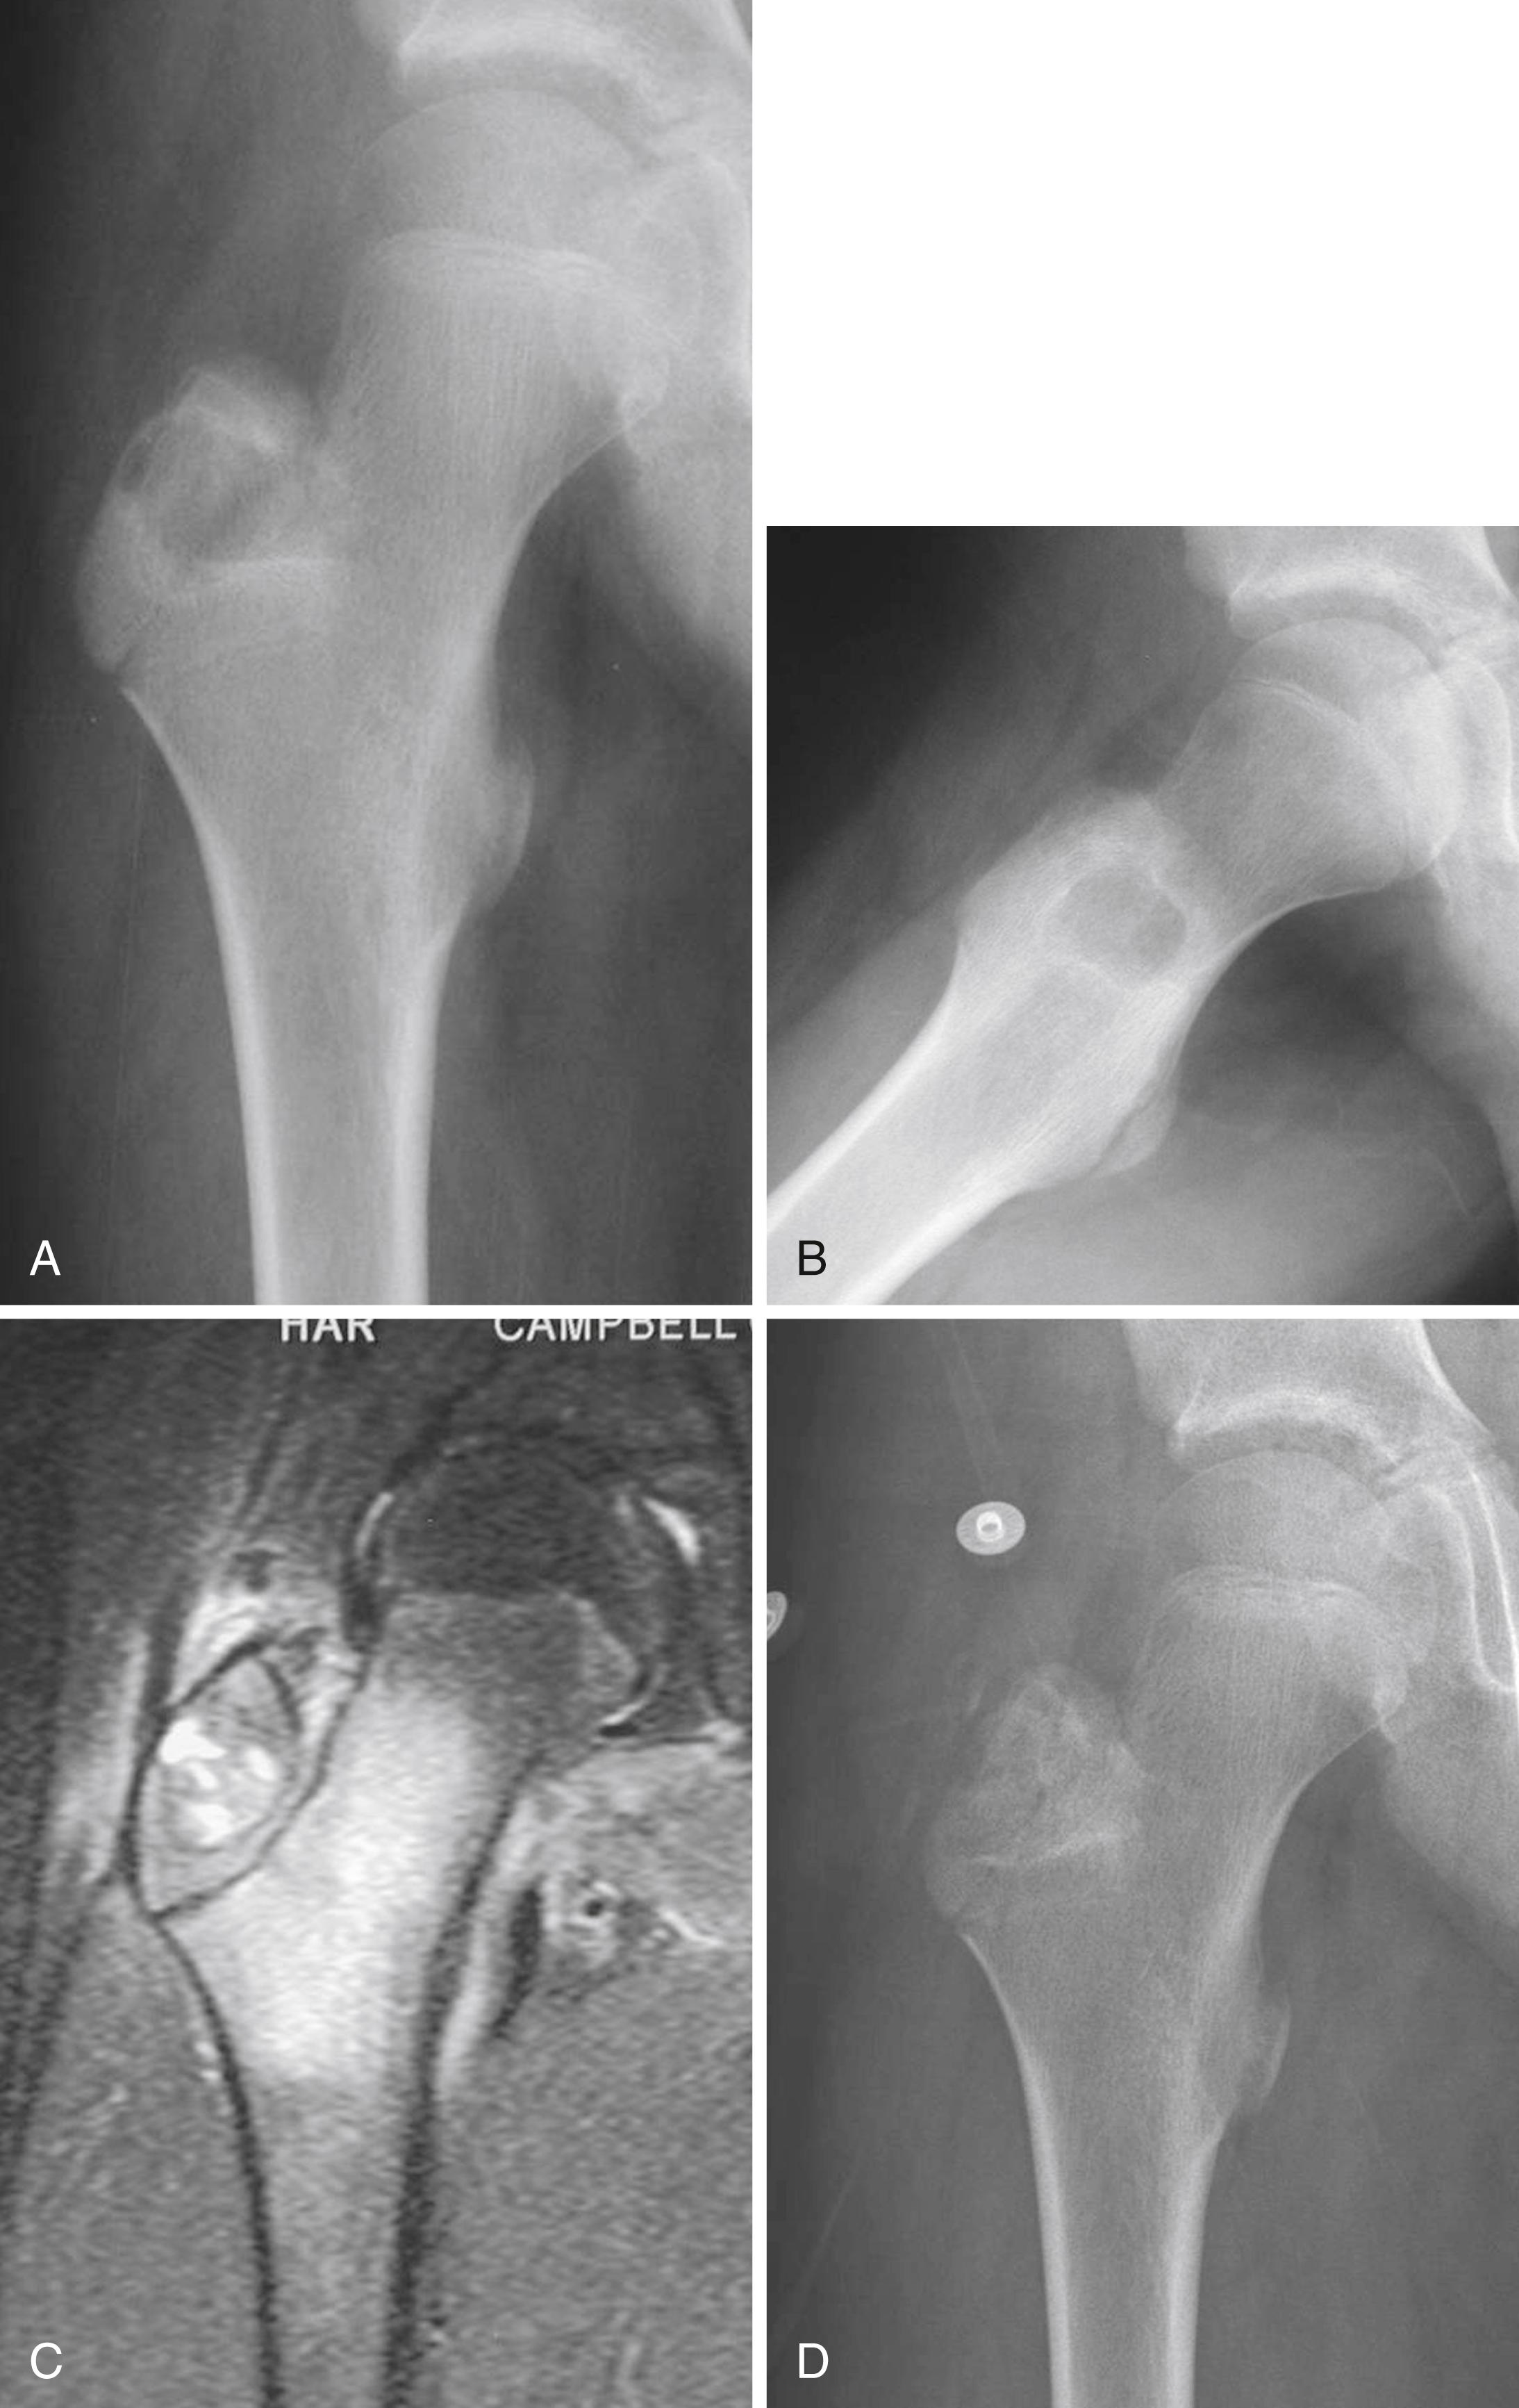

FIGURE 26.1, Giant cell tumor in a 21-year-old man.

FIGURE 26.2, A and B, Anteroposterior and lateral radiographs of the proximal tibia of a 41-year-old woman with a giant cell tumor. The lesion is radiolucent without a sclerotic rim, is eccentric, and abuts subchondral bone. C and D, Anteroposterior and lateral radiographs of the proximal tibia after curettage and placement of cement and divergent screws.